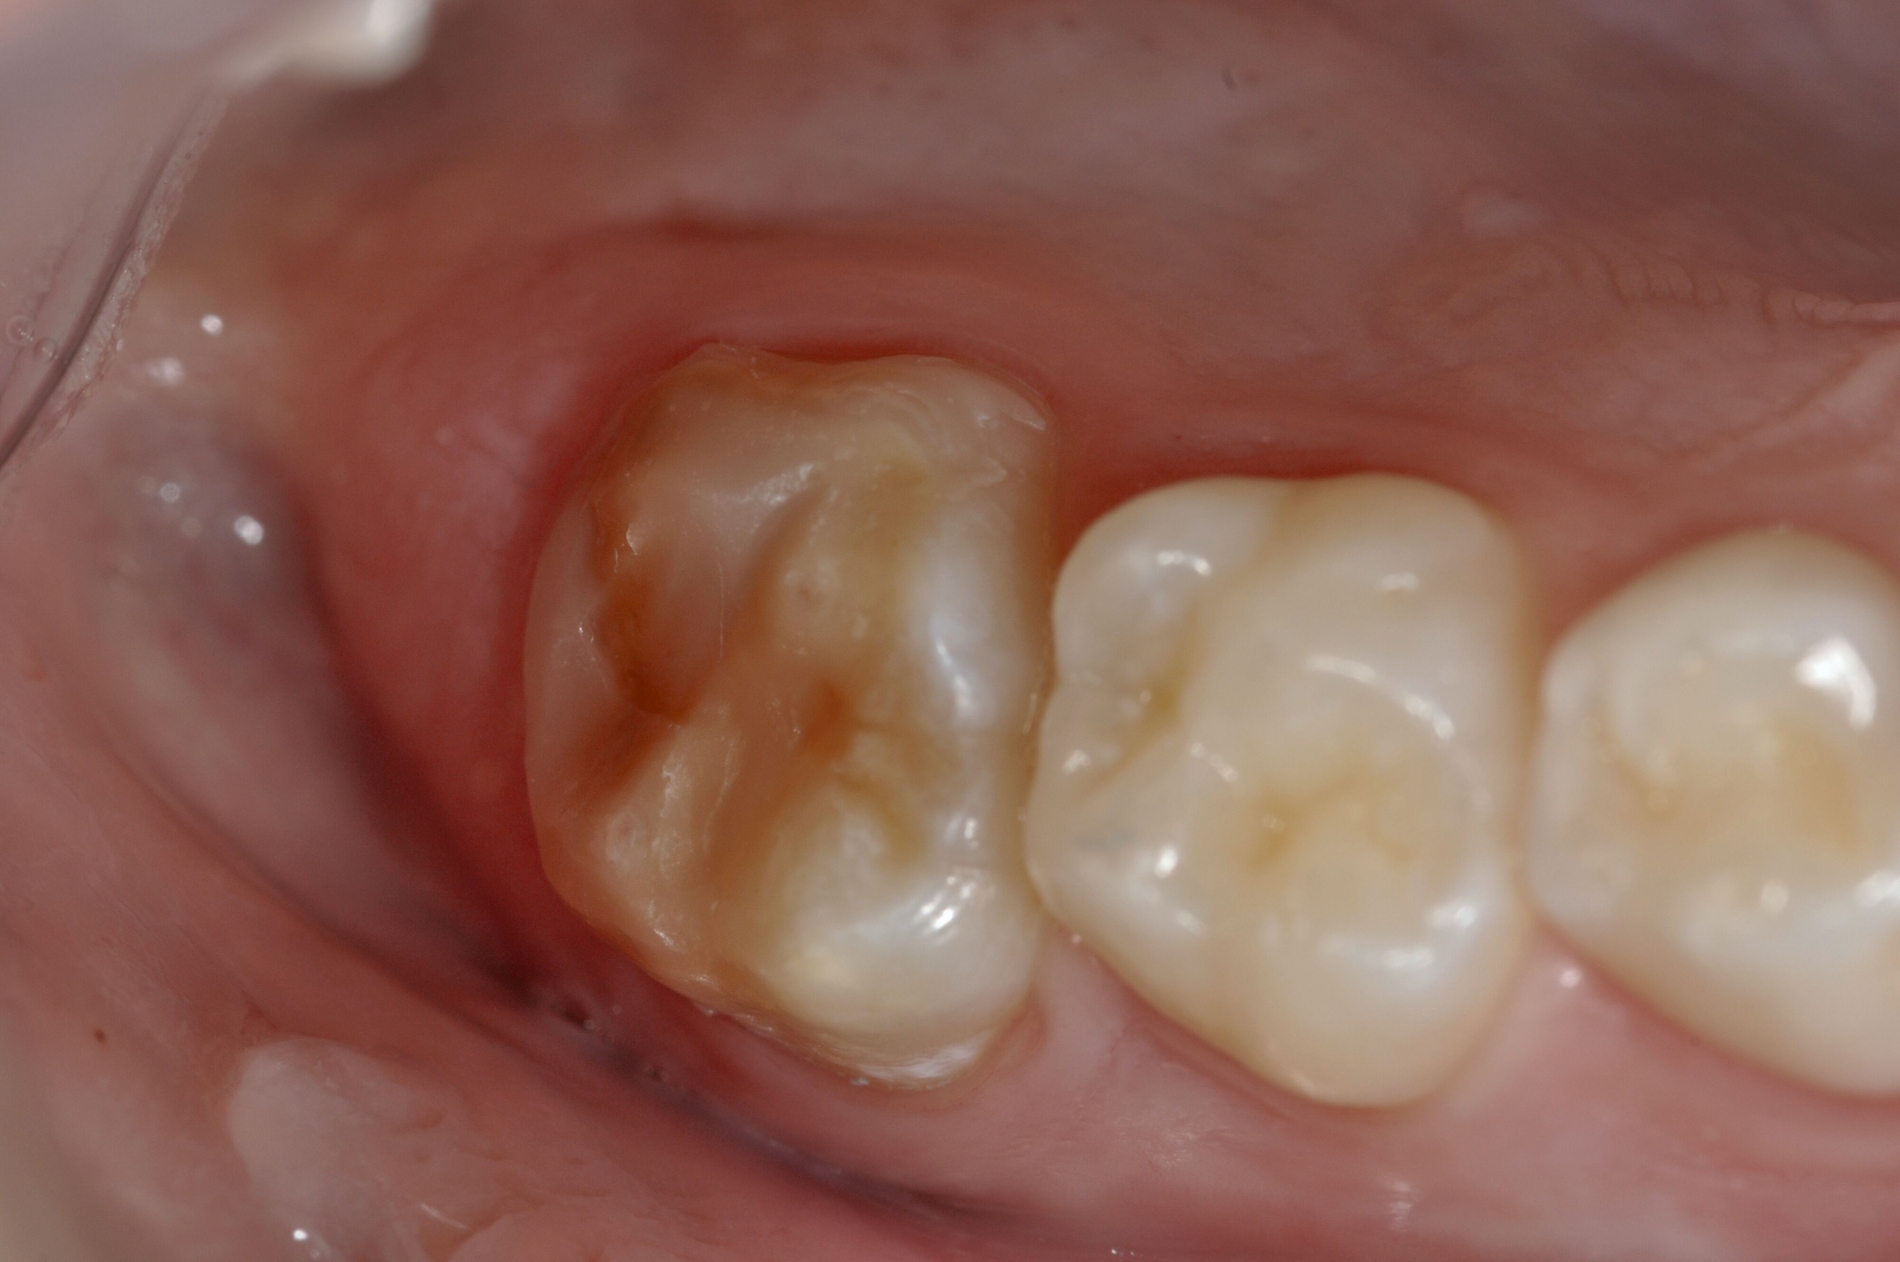

Die Therapie C hat das Ziel, MIH-Zähne vorübergehend zu versorgen, bis der vollständige Durchbruch der Zähne eine adhäsive Restauration ermöglicht, um die hypersensiblen Zähne zu desensibilisieren oder/und die Mitarbeit für die weitere Behandlung aufzubauen. Vor dem Hintergrund des erhöhten Kariesrisikos dieser Zähne (Abbildung 2) muss durch die Maßnahmen eine Kariesprogression vermieden werden.

Der Vorteil der Methode ist, dass die betroffenen Zähne auch ohne Lokalanästhesie und Präparation versorgt werden können. Die temporäre Versorgung ermöglicht es, die Patienten an die zahnärztliche Behandlung zu gewöhnen. Häufig führt diese temporäre Versorgung auch zu einer Reduktion der Hypersensitivität der MIH-Zähne. Nachteil der GIZ-Versorgung ist das Risiko einer Füllungsfraktur oder eines vollständigen Verlusts der Füllung (Abbildung 4). Aktuelle Erhebungen bestätigen eine Erfolgsrate von über 80 Prozent nach einem bis zwei Jahren [Durmus et al., 2021; Mahfouz et al., 2025].

Der Behandlungsfall (Abbildung 4d) veranschaulicht die Schwächen des Verfahrens. Wird das Angebot der regelmäßigen Kontrollen nicht wahrgenommen, so droht bei Verlust der Füllung die Kariesprogression. In dem vorliegenden Fall konnte jedoch eine endodontische Maßnahme vermieden und durch die selektive Kariesentfernung die Zahnhartsubstanz weitestgehend erhalten werden.